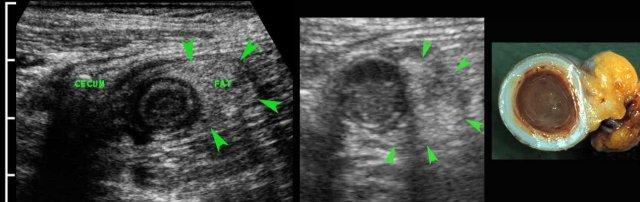

Điều thú vị là trong giai đoạn sớm của viêm mô mỡ, siêu âm nhạy hơn CT.

Ở bệnh nhân này với đau hố chậu phải kéo dài 18 giờ, CT chỉ cho thấy hình ảnh thâm nhiễm mỡ tối thiểu xung quanh ruột thừa 8,5 mm (mũi tên).

Siêu âm với kỹ thuật ép có kiểm soát đã cho thấy rõ ràng mô mỡ viêm tăng âm, không thể ép xẹp (đầu mũi tên) xung quanh ruột thừa.